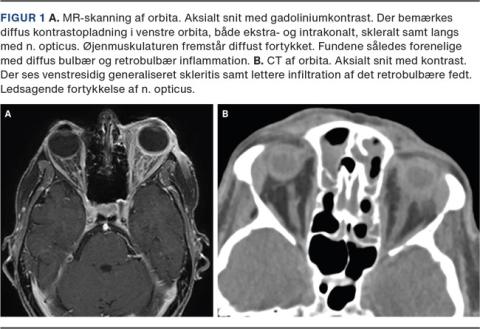

På dagen for den første zoledronsyreinfusion fik hun typiske influenzasymptomer. Et døgn efter tilkom der venstresidige øjengener med rødme og hævelse af øjenomgivelserne samt konjunktival injektion og tåreflåd. Hun havde ikke sinonasale gener eller febrilia. Visus var 0,8/>0,5, og øjentrykket var normalt (16/19 mmHg). Der var venstresidig proptose og let diffus bevægeindskrænkning med diplopi i yderpositionerne. Spaltelampeundersøgelsen viste vandig kemose og let hyperæmi samt enkelte celler i øjets forkammer. De biokemiske værdier var normale fraset let CRP-forhøjelse. Ved en MR-skanning af orbita med kontrast (Figur 1A) blev der påvist retrobulbær inflammation samt inflammation skleralt og langs synsnerven.

II. En 54-årig kvinde begyndte i behandling med tablet alendronat 70 mg ugentligt. I de efterfølgende uger fik hun smerter omkring venstre øje, der ligeledes fremstod injiceret. Der var episodisk forværring, typisk et par dage efter medicinindtag. Tilstanden blev af en øjenlæge initialt tolket som viral konjunktivitis og siden som migræne under indlæggelse i medicinsk regi. Ved vurdering i vores regi fandtes bevægerelaterede retrobulbære smerter. Visus (1,2/1,2) og øjentryk (13/13 mmHg) var normale. Spaltelampeundersøgelse og oftalmoskopi var upåfaldende fraset let, overvejende konjunktival, injektion. Ved UL-skanning af øjet og CT af orbita med kontrast (Figur 1B) blev der påvist posterior skleritis samt let inflammation i det retrobulbære fedt og langs synsnerven. Ophør af behandlingen suppleret med peroral prednisolon ledte til remission.